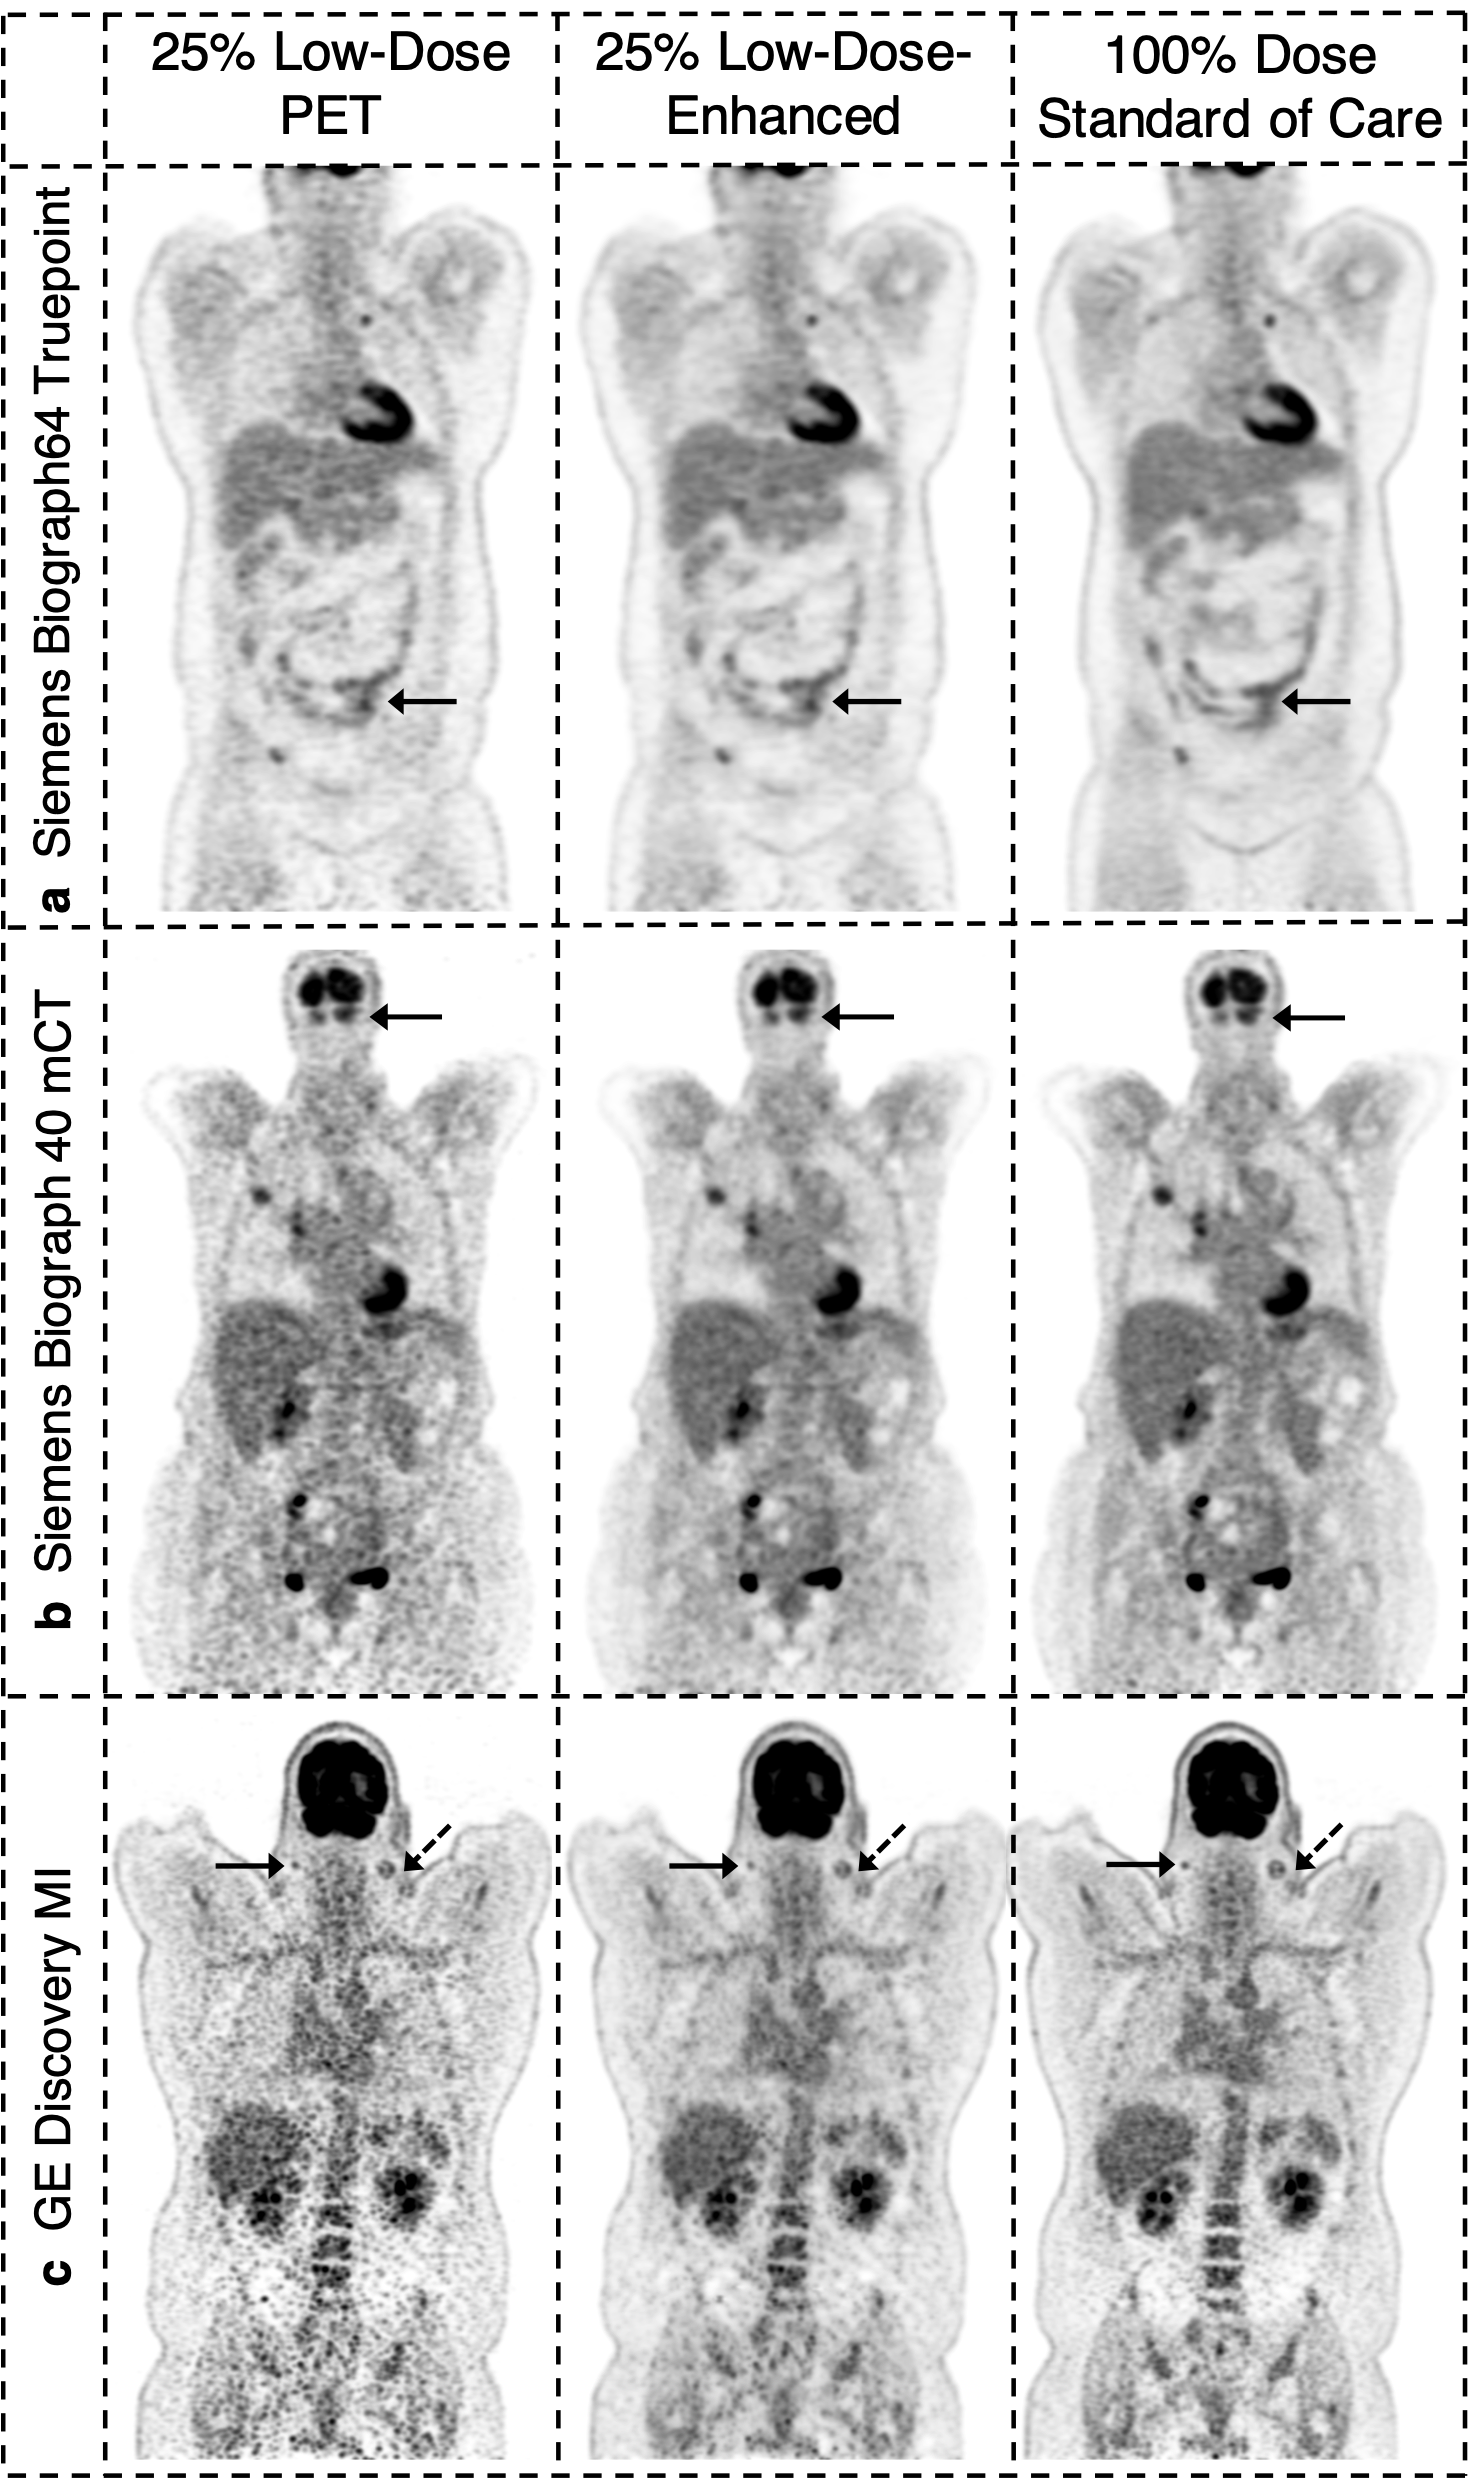

An example image of subjects scanned on three different PET scanners with body mass index (BMI) of over 30 is shown below. Traditionally, PET scans are sensitive to varying body habitus and suffer from low signal-to-noise ratio in subjects with higher BMI. We demonstrate how our method improves the diagnostic image quality of low-count PET scans even in high BMI patients.